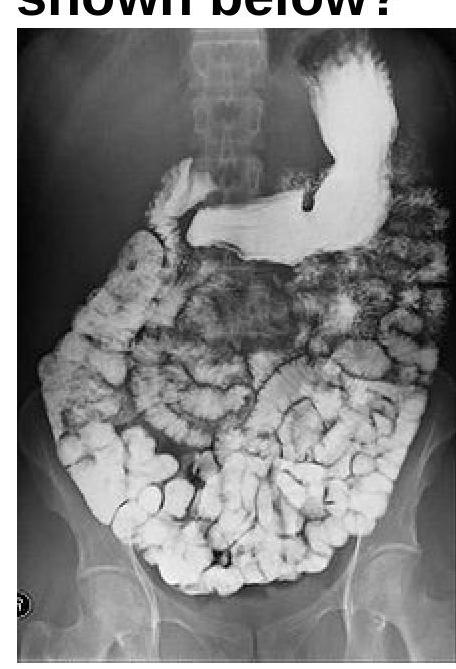

Question 4: Identify the radiological procedure shown in the image?

- A. Barium meal follow through (Correct Answer)

- B. Barium enema

- C. Enteroclysis

- D. Proctography

Explanation: ***Barium meal follow through*** - The image shows opacification of the stomach and the entire small bowel loops via oral uptake of a contrast agent, which is characteristic of a **barium meal follow-through**. - This procedure tracks the passage of **barium** from the esophagus, stomach, and duodenum, through the jejunum and ileum, to assess the **small intestine's morphology and function**. *Barium enema* - A **barium enema** involves introducing contrast material rectally to visualize the **colon and rectum**, which is not depicted in this image. - The primary structures opacified in a barium enema are the **large intestine**, not the stomach and small bowel as seen here. *Enteroclysis* - **Enteroclysis** is a specialized study of the small bowel where contrast is directly instilled into the **duodenum** or **proximal jejunum** via a nasoenteric tube. - While it visualizes the small bowel, the image shows oral contrast progression from the stomach, not direct jejunal intubation. *Proctography* - **Proctography**, also known as defecography, is a dynamic study focused specifically on the **rectum and anal canal** during defecation. - This procedure is highly specific to the distal gastrointestinal tract for assessing anorectal function and does not visualize the stomach or extensive small bowel loops.